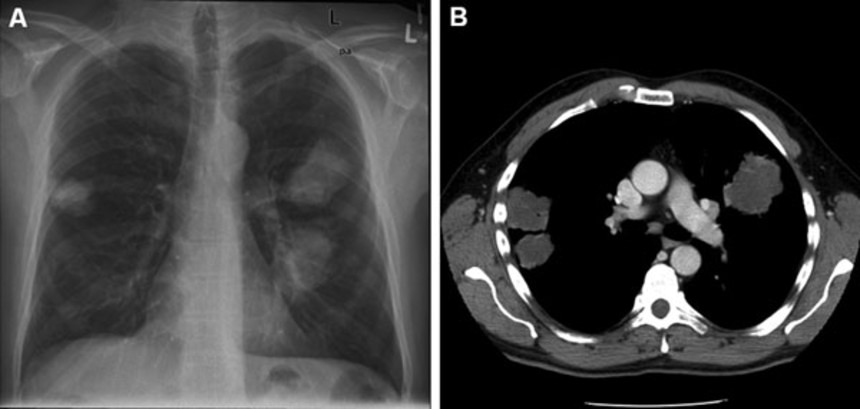

感染した人のレントゲン写真